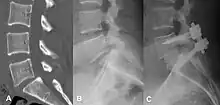

| X-ray of the lateral lumbar spine with a grade III anterolisthesis at the L5-S1 level | |